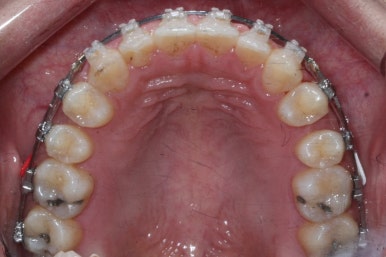

전반적으로 흩어져 있던 틈새를 특정 위치로 모으기 시작합니다.

앞니 사이의 틈을 제일 보기 싫어하실 것 같으므로 앞니 부터 빠르게 틈을 보아줍니다. 대신 작은 어금니 부위로 틈을 모으는 작업을 하게 됩니다.

점점 앞니 사이의 틈이 없어지는 것을 볼 수 있습니다.

앞니 사이의 없어진 틈은 대신 작은 억므니 부위로 모여져 갑니다.

앞니 사이의 틈이 이제 다 모아졌습니다.

바로 미니스크류 입니다. 위 사진에서 화살표 부분이 바로 미니스크류 입니다.

뼈에 단단히 고정해 놓고 어금니를 앞으로 당겨오는데 사용을 하게 됩니다. 교정치료 후에는 제거하게 되며 긍방 뼈가 차기 때문에 별로 걱정은 하지 않으셔도 됩니다.